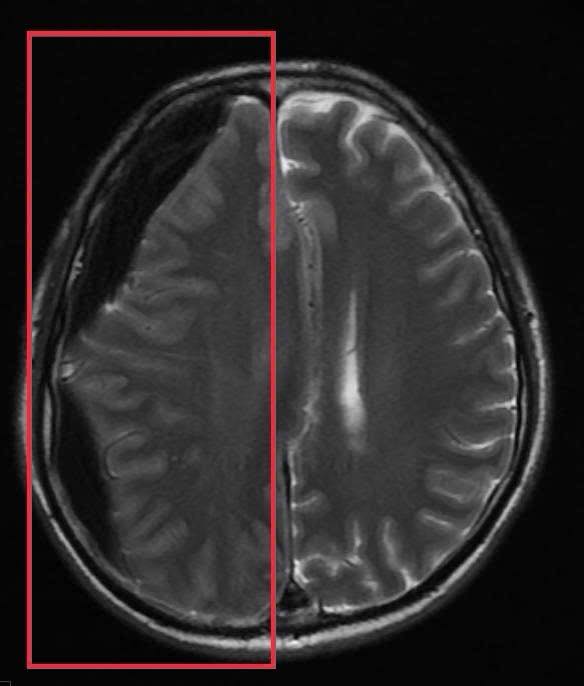

Trước băn khoăn của gia đình, BS Huyền đã tư vấn ưu tiên chụp MRI sọ não. Kết quả chụp MRI sọ não cấp đã xác định người bệnh có khối tụ máu não dưới màng cứng mạn tính kích thước lớn vùng thái dương, gây hiệu ứng khối và đè đẩy đường giữa của não. Đây là tình trạng đặc biệt nguy hiểm, bởi khối tụ máu có thể tiến triển âm thầm trong nhiều tuần với triệu chứng kín đáo như chậm chạp, giảm trí nhớ, rối loạn ngôn ngữ nhưng có nguy cơ cao dẫn đến liệt vận động, tụt kẹt não, hôn mê và tử vong nếu không được xử trí kịp thời

Ngay sau khi có kết quả chẩn đoán hình ảnh, ông P.V.D được chuyển sang chuyên Khoa Phẫu thuật thần kinh sọ não để phẫu thuật cấp cứu lấy bỏ tụ máu, giải phóng chèn ép nhu mô não. Đồng thời, người bệnh được chỉ định điều trị thuốc kháng động kinh do đã có nhiều cơn co giật rõ ràng trước đó. Sau can thiệp, tình trạng ý thức cải thiện tốt, không xuất hiện cơn co giật.